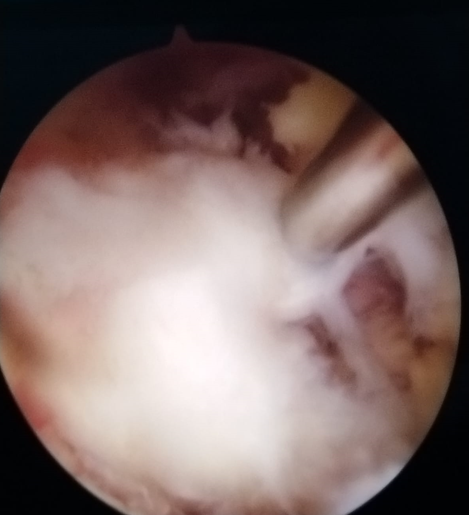

Проведение операции: через трубку хирург вводит эндоскоп — небольшую камеру, которая обеспечивает чёткое изображение внутри позвоночника. С помощью специальных инструментов хирург удаляет проблемные ткани, такие как грыжи межпозвоночных дисков или костные наросты, которые могут давить на нервы и вызывать боль. В отличие от некоторых клиник, которые рекламируют «лазерную операцию на позвоночнике», мы используем комбинацию инструментов, в том числе лазер и ультразвуковую энергию, чтобы точно воздействовать на проблемную область.

Завершение операции: после освобождения спинномозговых нервов от давления хирург часто вводит небольшую дозу стероидного препарата непосредственно в поражённую область, чтобы уменьшить воспаление и улучшить самочувствие после операции. Затем инструменты извлекаются, а небольшой разрез закрывается одним швом и крошечной повязкой.